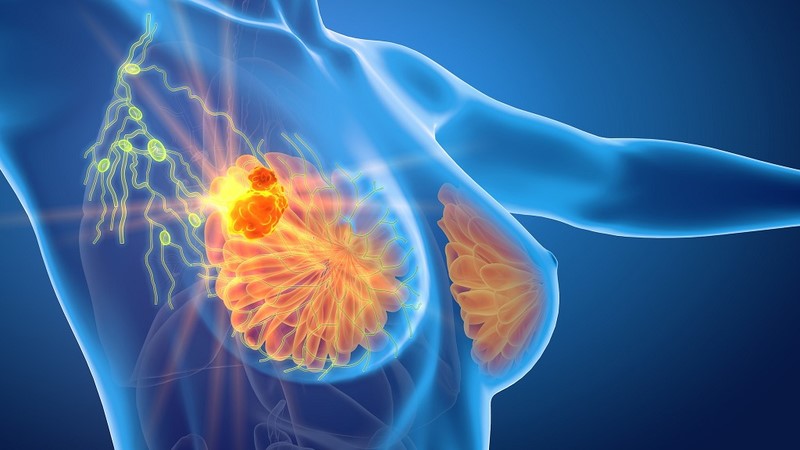

Ung thư vú là một trong những bệnh ung thư phổ biến nhất ở phụ nữ. Tuy nhiên, nếu được phát hiện và điều trị ở giai đoạn sớm, tỷ lệ chữa khỏi bệnh có thể lên đến 90%. Vì vậy, việc tầm soát định kỳ đóng vai trò vô cùng quan trọng. Trong các phương pháp tầm soát ung thư vú hiện nay, chụp nhũ ảnh được xem là kỹ thuật hàng đầu, mang lại cơ hội phát hiện sớm, giúp phụ nữ chủ động bảo vệ sức khỏe của mình.

Chụp nhũ ảnh là một kỹ thuật chẩn đoán hình ảnh, sử dụng một lượng tia X rất nhỏ để chụp lại hình ảnh chi tiết bên trong mô vú. Đây là một phương pháp không xâm lấn, đơn giản và nhanh chóng, có khả năng phát hiện những tổn thương, khối u rất nhỏ mà người bệnh và thậm chí cả bác sĩ không thể sờ thấy được. Hình ảnh thu được từ máy chụp nhũ ảnh sẽ giúp các chuyên gia y tế đánh giá chính xác cấu trúc tuyến vú và phát hiện các dấu hiệu bất thường.

Chụp nhũ ảnh có khả năng phát hiện những vi vôi hóa (những đốm canxi nhỏ) hoặc các tổn thương rất nhỏ mà khám lâm sàng và siêu âm có thể bỏ sót. Những dấu hiệu này thường là manh mối sớm nhất của ung thư.

Theo BSCKII Mai Văn Bảo, chuyên ngành Chẩn đoán hình ảnh, chụp nhũ ảnh được sử dụng với 2 mục đích là để tầm soát và chẩn đoán các bệnh lý về tuyến vú:

- Chụp nhũ ảnh tầm soát: Chụp nhũ ảnh phát hiện những thay đổi ở vú ở những phụ nữ không có dấu hiệu hoặc triệu chứng của bệnh ung thư vú. Phương pháp này có thể phát hiện ra khối u mà không thể sờ thấy được.

- Chụp nhũ ảnh chẩn đoán: Chụp nhũ ảnh với mục đích chẩn đoán khi có những thay đổi bất thường của vú, chẳng hạn như một khối u, đau vú, da vú dày hoặc tiết dịch núm vú, hoặc thay đổi kích thước hoặc hình dạng vú.

Chụp nhũ ảnh không phải là bước cuối cùng trong chẩn đoán nhưng nó là một công cụ không thể thiếu trong quá trình tầm soát và chẩn đoán ung thư vú, giúp bác sĩ có cái nhìn trực diện và chính xác về tình trạng của bệnh nhân. Nhờ đó, việc điều trị có thể được tiến hành kịp thời, giúp tăng hiệu quả chữa bệnh, giảm chi phí và đặc biệt là nâng cao đáng kể cơ hội sống cho người bệnh.